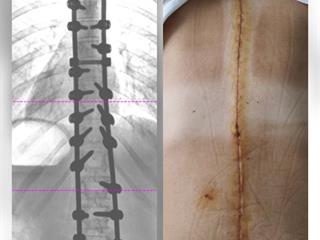

Potom sa jej v priebehu krátkej doby natoľko zhoršila skolióza, až musela ako 15 ročná podstúpiť operáciu chrbtice. Operácia sa podarila, voperovali jej kovovú konštrukciu pozdĺž chrbtice, ale... Po operácii jej zostali bolesti, asymetria ramien, zrotovaná panva a krčná chrbtica. Je to teda problém jednak estetický, ale aj zdravotný. Samozrejme u 15-ročného dievčaťa dostáva zabrať aj psychika, keď musí v puberte riešiť takéto problémy . V každom prípade jej už doživotne ostanú obmedzenia. Chceme však dosiahnuť aby boli čo najmenšie. Veď už si v mladom veku celkom vytrpela. Podľa lekárov to môže zlepšiť dlhodobá intenzívna rehabilitácia a fyzioterapia. Tú základnú vo forme kúpeľov uhradila poisťovňa, ale ďalšie už musí absolvovať ako samoplatiteľ. Momentálne študuje diaľkovo na gymnáziu, keďže bežný vyučovací proces ešte nezvláda. Rehabilitácia a fyzioterapia týždenne stojí cca 170 euro, čo je z dlhodobého hľadiska mimo našich finančných možností. Ja ako otec som invalidný dôchodca so sklerózou multiplex a matka - moja manželka ma opatruje. Chceli by sme vrátiť dcére úsmev na pery aj do duše. Sami to ale nezvládneme a preto hľadáme touto cestou pomoc. Chceme spraviť napriek našim obmedzeným možnostiam všetko pre našu dcéru.